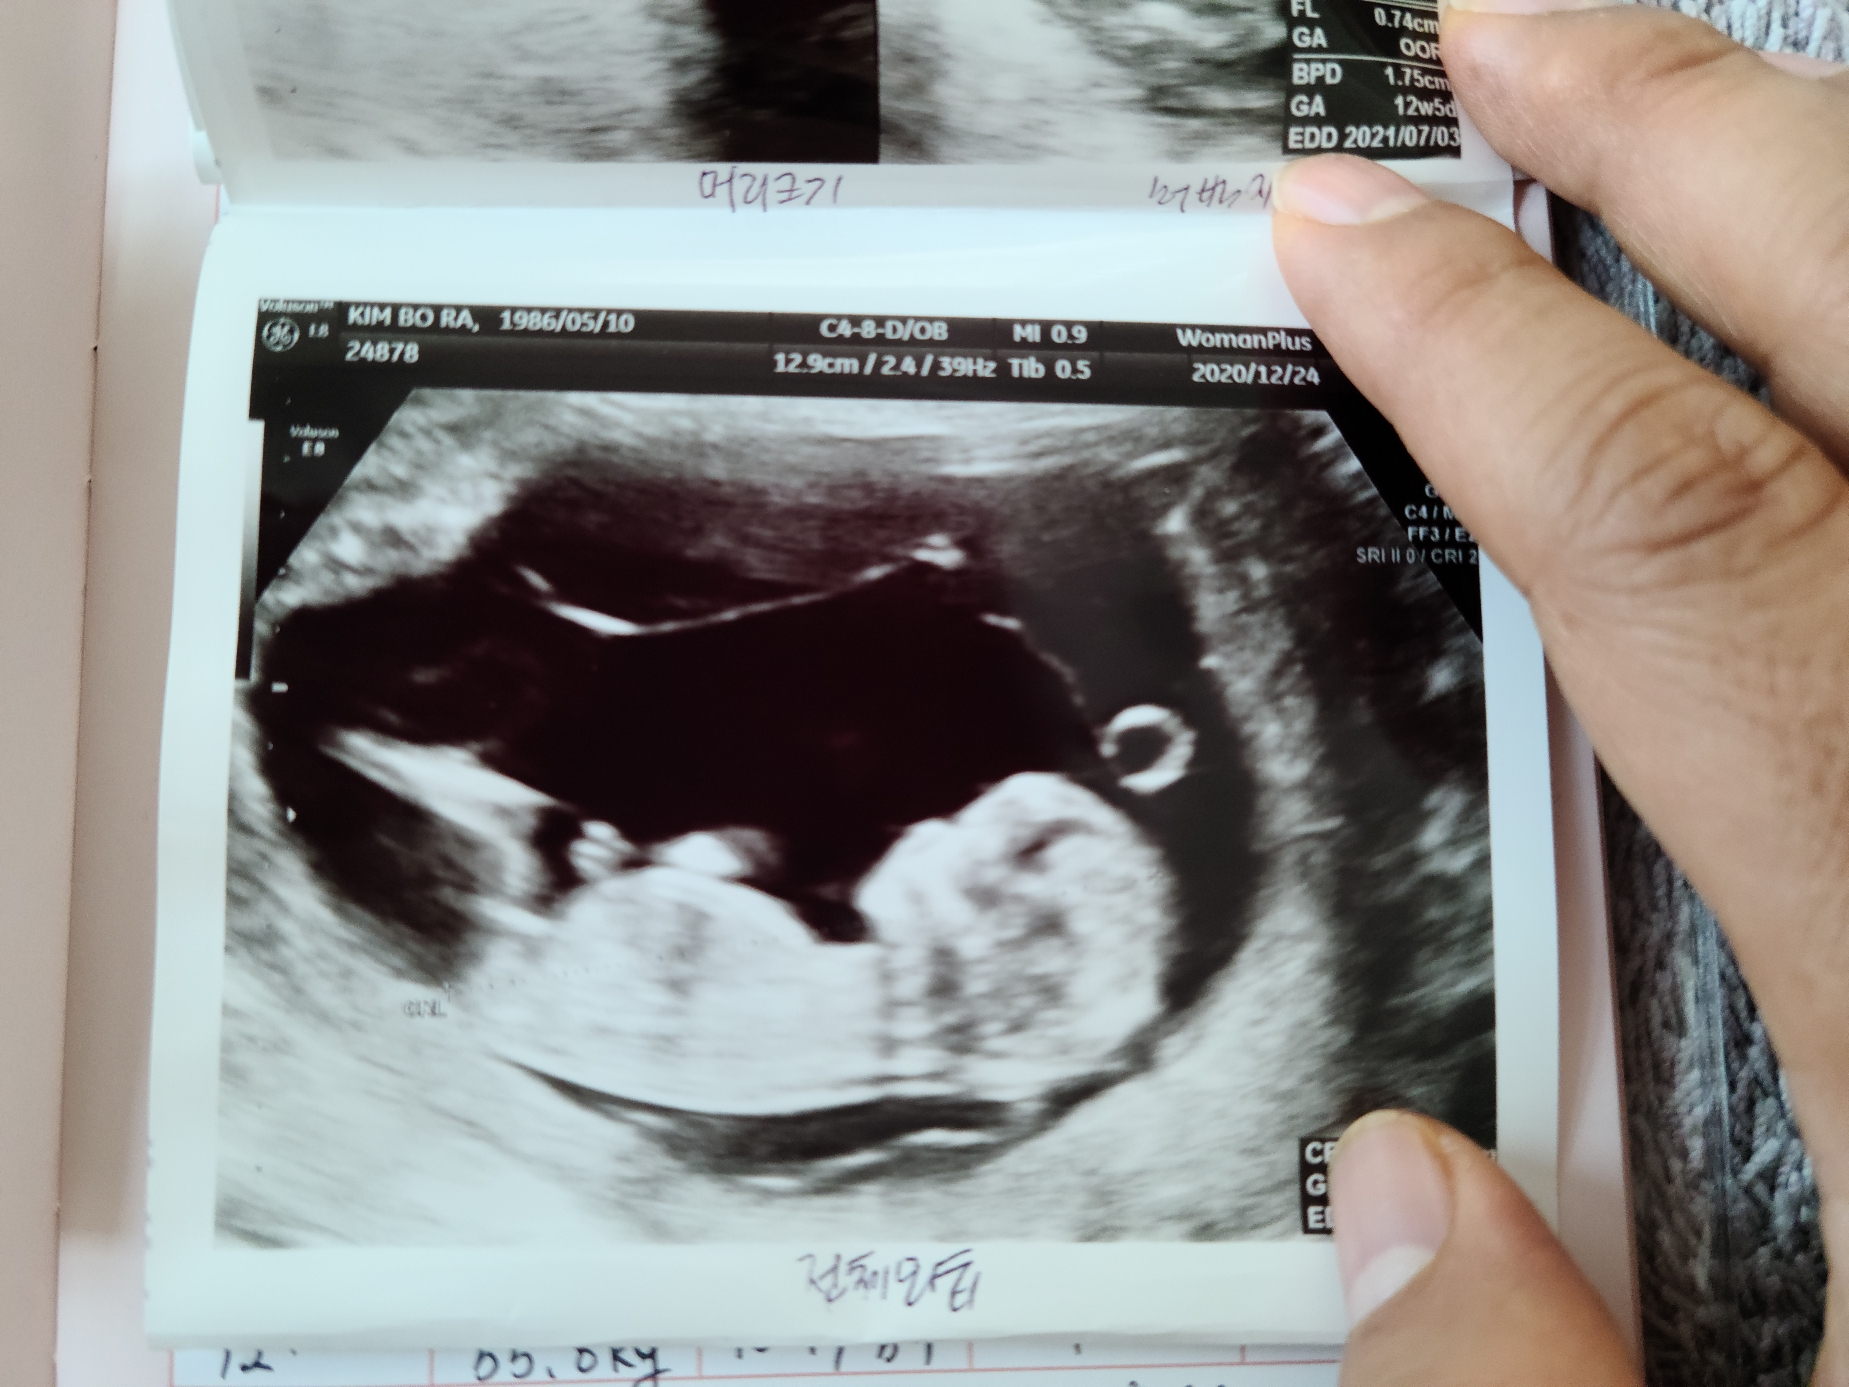

불안한 마음에 병원에 가서 검사한 결과 다행히 아무런 이상없이 건강하게 자라고 있음을 확인했어.

엄마 뱃속에서 뛰고 있는 무탈이 심장을 보며 아빠는 고마움과 기쁘이 남쳐 눈물이 고였다.